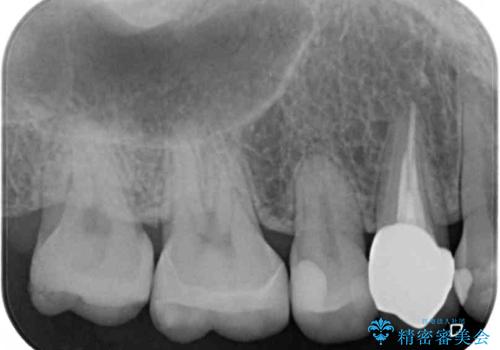

- 奥歯の詰め物や周辺の歯が欠けてしまったとのことで来院された患者様です。

上顎は、元々の詰め物が小さく、欠けた範囲も大きくなかったため、セラミックインレーにて修復治療を行うこととしました。

一方下顎は、元々のむし歯の範囲が広かったため、長期的な予後を踏まえ、セラミッククラウンにて補綴治療を行うこととしました。